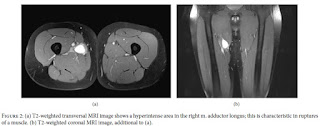

Radiografias convencionais da pélvis e anca direitos não

apresentaram anormalidades ósseas. A ressonância magnética (RM) revelou uma

região de hipersinal intramuscular no adutor longo, com comprimento

craniocaudal de 4,2 centímetros. Não houve retração do músculo.

Com base nos achados clínicos e na ressonância magnética o

diagnóstico foi feito: uma ruptura intramuscular do adutor longo.

O exame de RM adicional mostrou hipersinal subtil em imagens

ponderadas em T1 na zona da rutura anterior do adutor longo, sem quaisquer

anormalidades estruturais. Os achados foram discutidos com o paciente e nenhum

tratamento adicional foi iniciado.